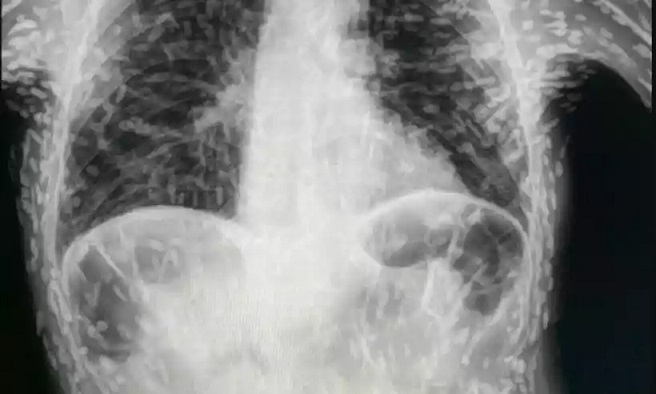

O médico Vitor Borin compartilhou nas redes sociais um caso preocupante envolvendo um paciente com cisticercose disseminada, uma doença causada pela ingestão de ovos do verme tênia. O exame de raio-x mostrou várias marcas brancas, que eram larvas do parasita, espalhadas pelo corpo do paciente.

O indivíduo sofria de tosse persistente há mais de dois meses, levando o médico a solicitar uma radiografia do tórax. O exame revelou a presença de tênias nos braços e no peitoral do paciente. A cisticercose disseminada ou muscular ocorre quando as larvas infestam diversos órgãos ou tecidos, incluindo pele, tecido celular subcutâneo, músculos, cérebro e olhos.

HPMA: Tosse há 2 meses.*Solicito radiografia de tórax*A radiografia: pic.twitter.com/x42A0Q3eXf— Vitor Borin P. de Souza (@vitorborin_) April 16, 2023

Segundo Dr. Vitor Borin, o tratamento para cisticercose depende da presença de lesões intracranianas, medulares ou oculares. Pacientes assintomáticos e sem acometimento do sistema nervoso central geralmente não precisam de tratamento. No caso específico do paciente em questão, as lesões estavam calcificadas, indicando que os cisticercos não eram viáveis. Se não houver desconforto, o paciente pode continuar sua vida normalmente.